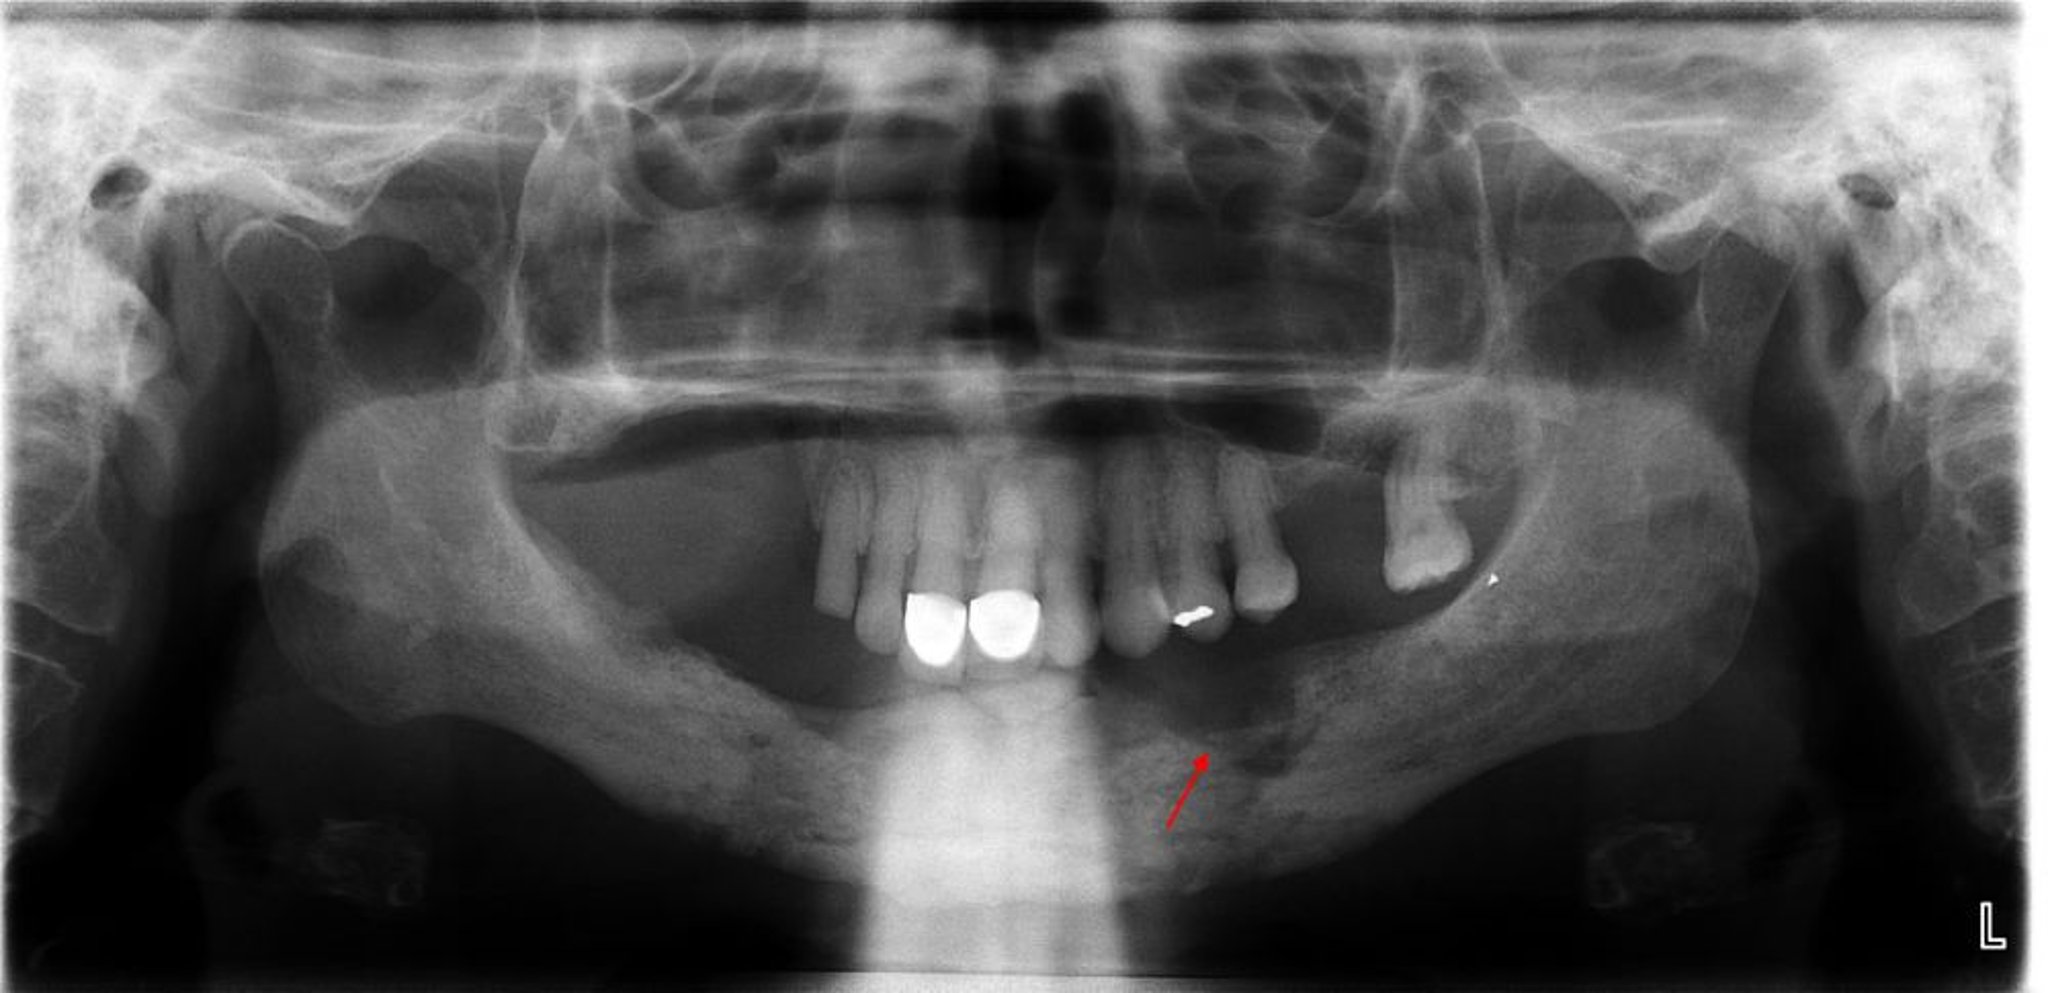

Ostéomyélite

Cette radiographie montre une ostéomyélite avec un séquestre (os non viable) évident visible dans le quadrant mandibulaire gauche (flèche).

Image courtoisie de Byron (Pete) Benson, DDS, MS, Texas A&M University Baylor College of Dentistry.